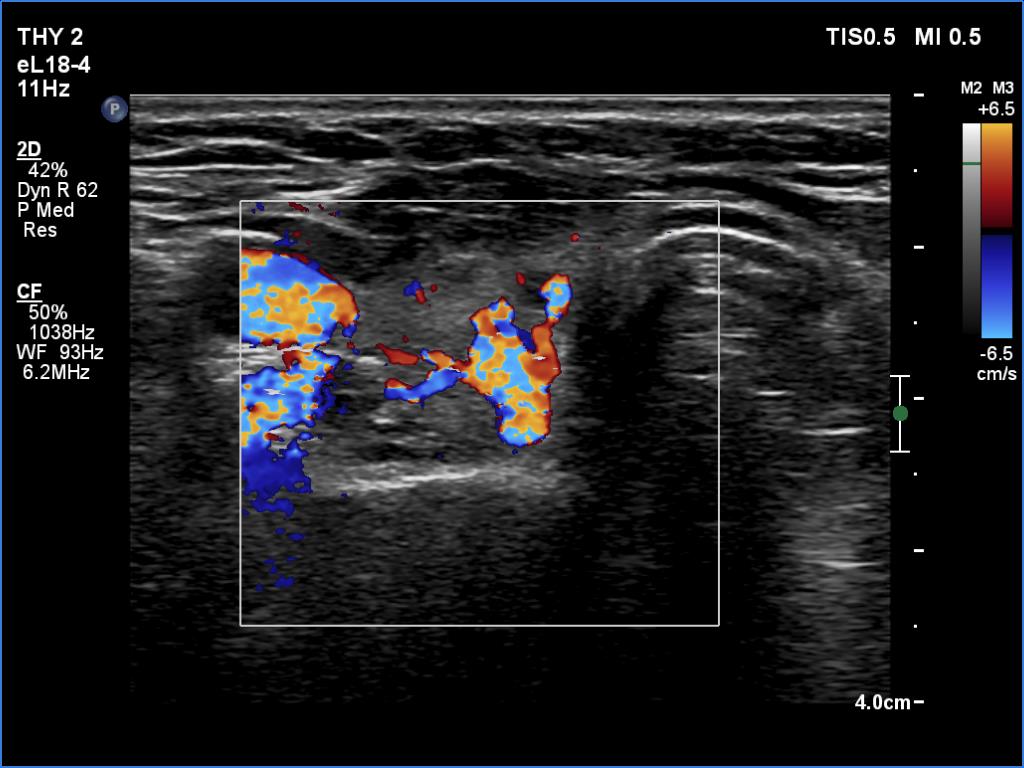

Follow-up investigation 6 months after first visit (ultrasonographic picture 6)

Right lobe, transverse view, color Doppler mode.